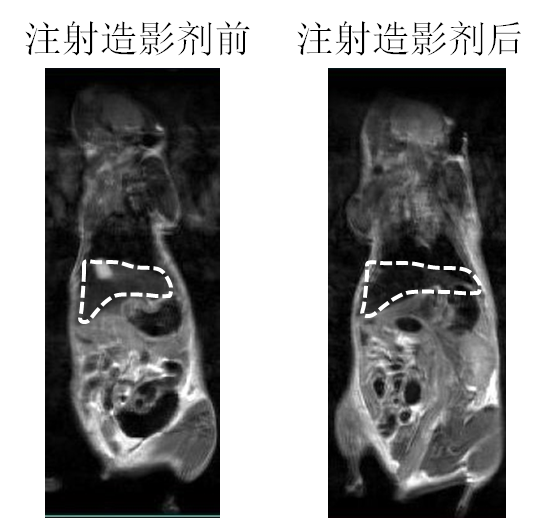

´ÅÐÔÄÉÃײÄÁÏ×÷Ϊ´Å¹²Õñ£¨MRI£©ÔìÓ°¼ÁµÄÓ¦ÓÃ